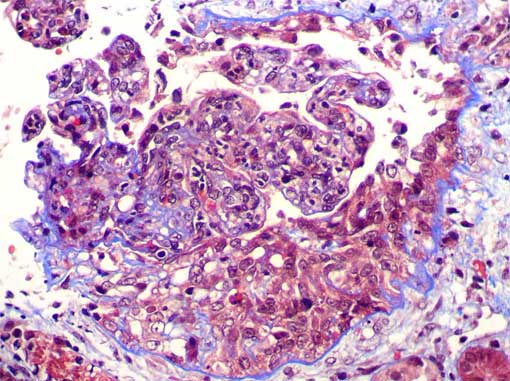

Figure 5.

Masson's trichrome stain, X400.